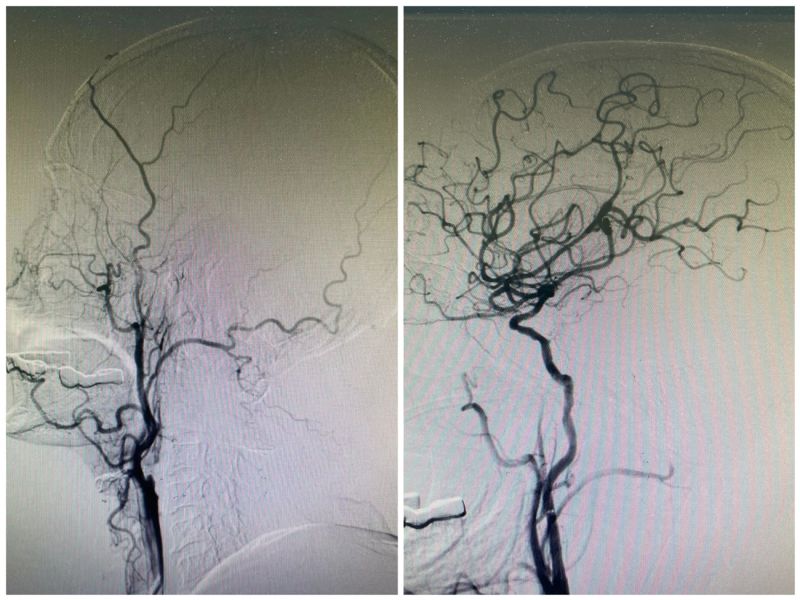

患者对今后的生存质量要求比较高,因此仍要尽可能寻求手术抢救机会。唐剑华主任医师再次联系医学影像科急行头CT灌注成像检查(CTP),评估梗死核心区与低灌注区情况。结果令人欣喜,经过指标评估,患者有扩大时间窗动脉取栓指征。征得家属同意后,紧急联系介入医学团队进行手术安排,短短20分钟患者就顺利到达介入手术室进行治疗,脑血管造影提示右侧颈内动脉闭塞并立即行急诊开通治疗。手术过程顺利,术后第二天患者症状就有明显改善,目前患者肢体活动已基本恢复正常,顺利出院。

取栓前后影像对比。